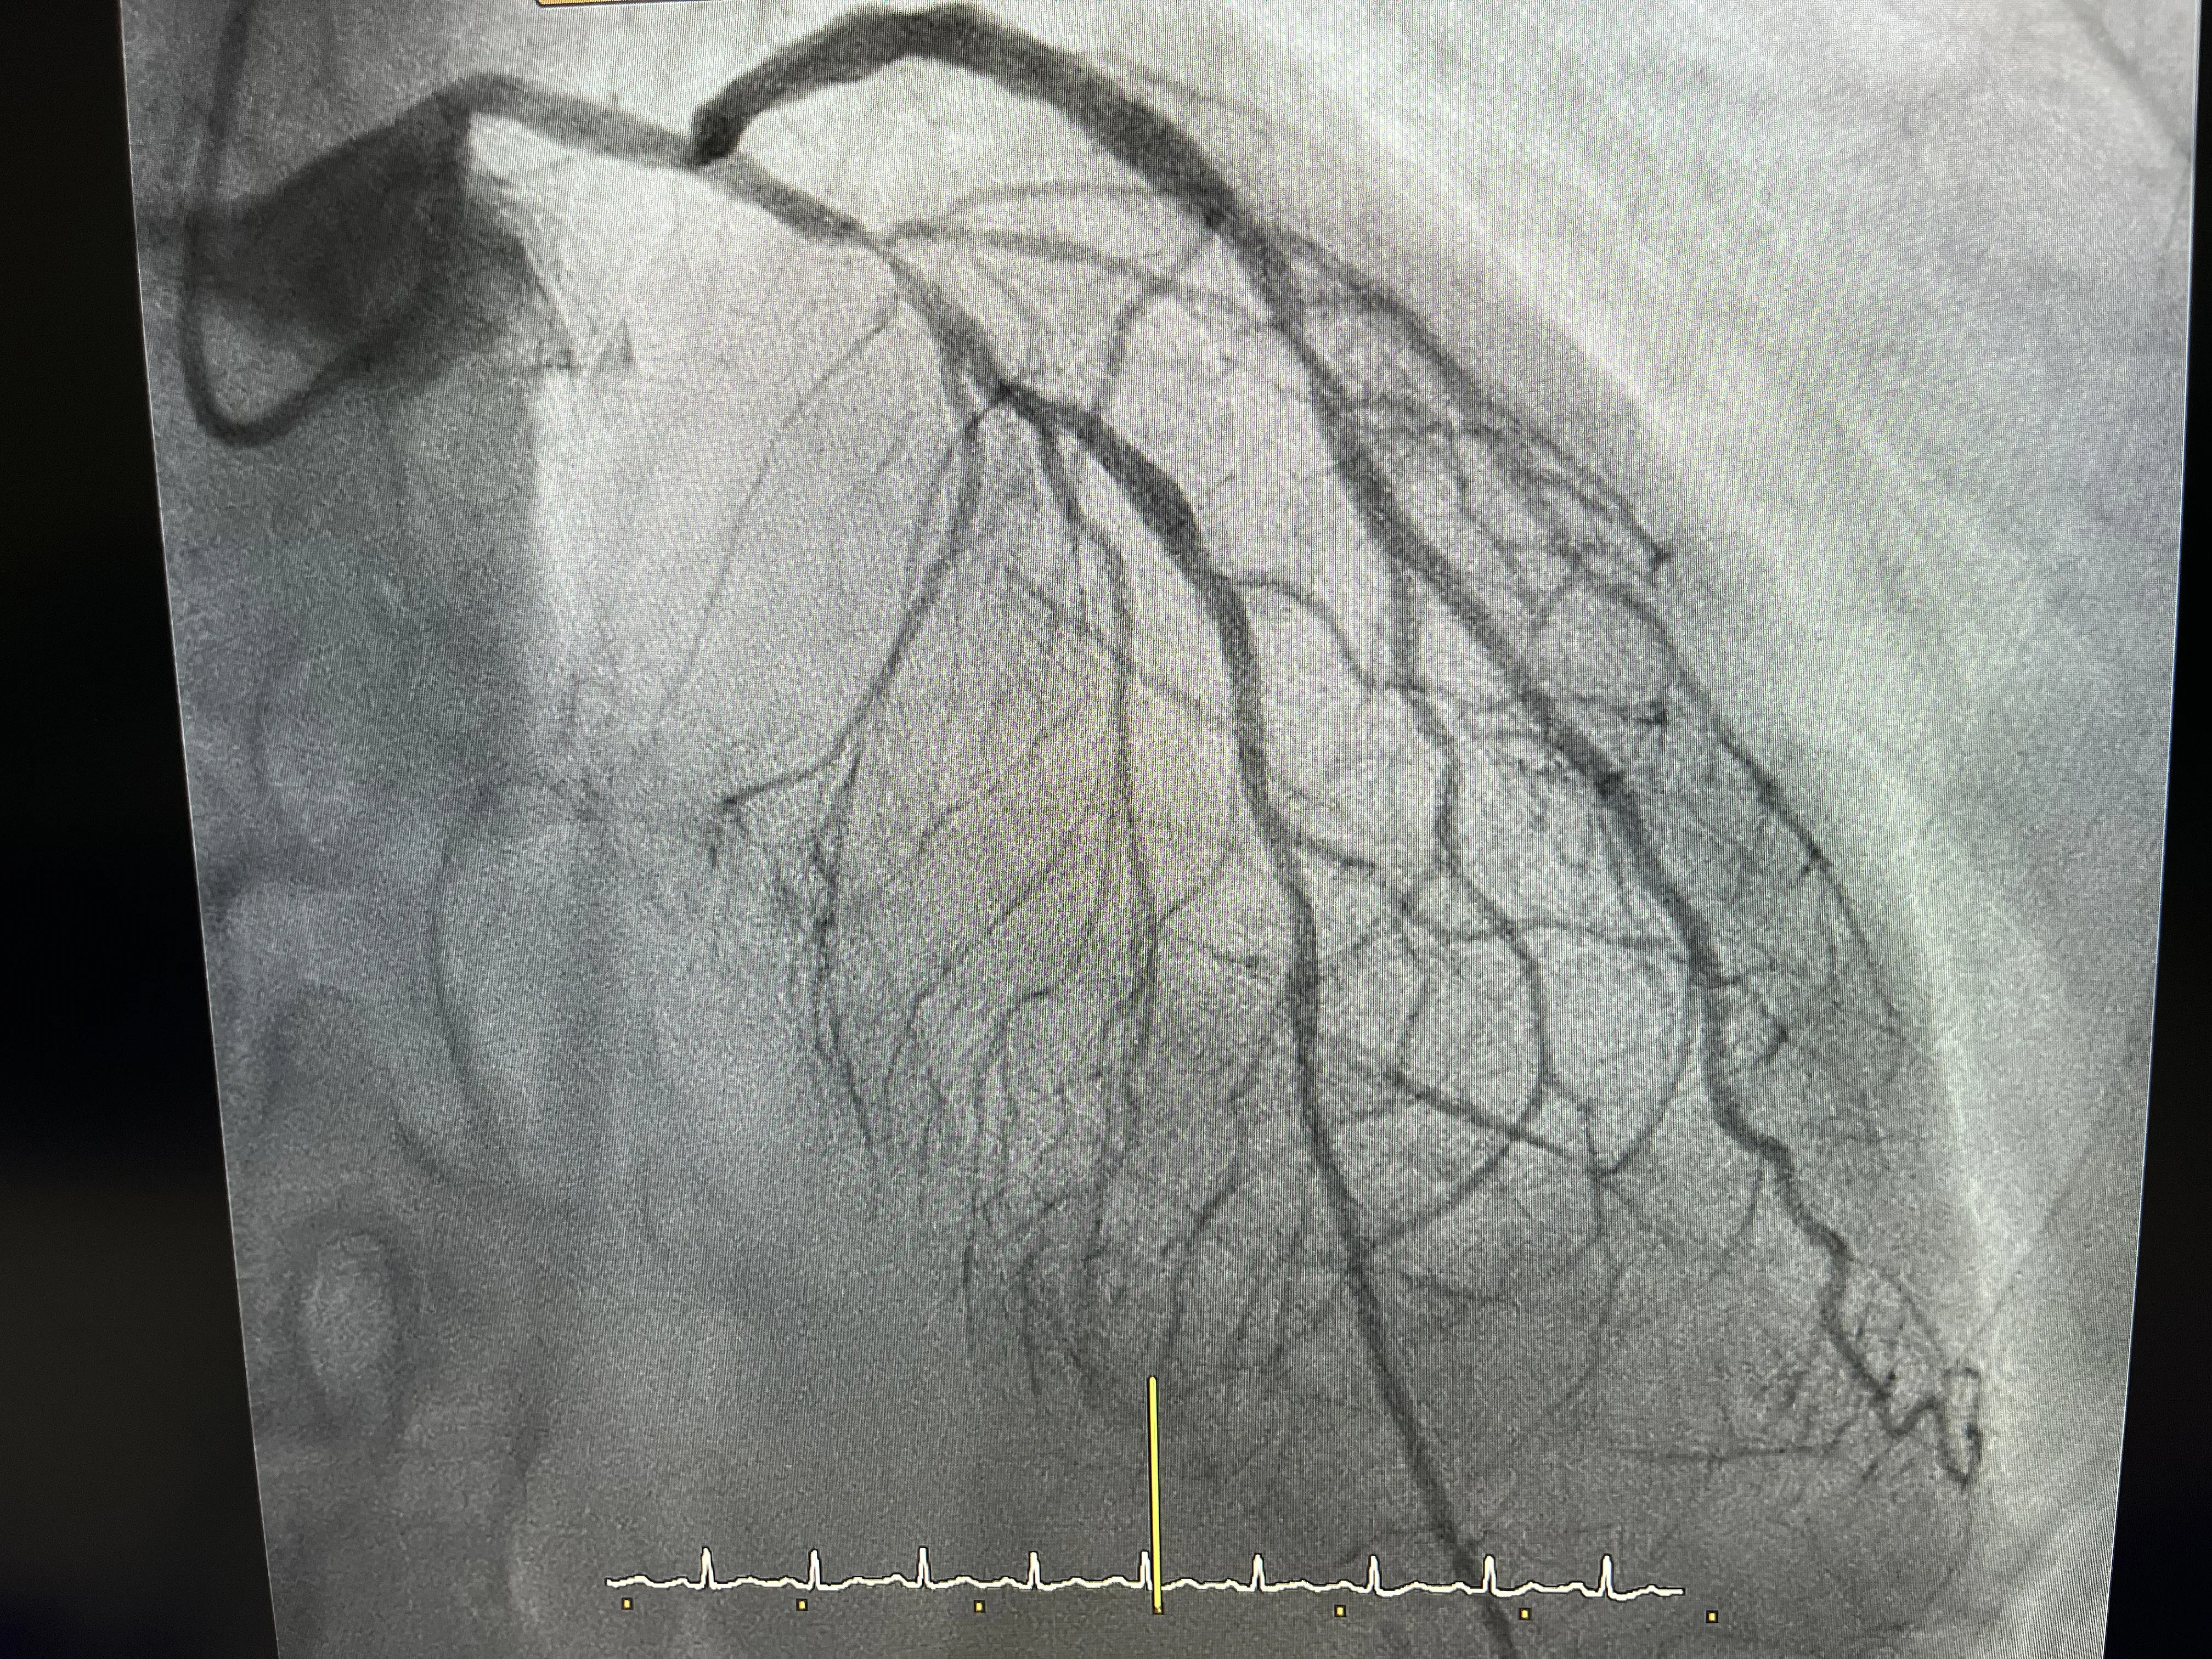

Predilatación de la lesión e implante del stent

Una vez confirmada la severidad de la lesión, se llevó a cabo la predilatación de la arteria afectada. Este procedimiento consiste en ensanchar temporalmente la arteria para facilitar la colocación del stent. El implante del stent se realizó sin complicaciones, asegurando que la arteria permaneciera abierta y permitiendo un flujo sanguíneo adecuado. Esta intervención fue crucial para prevenir un infarto y mejorar la calidad de vida del paciente.

Los casos de angina inestable, como el que se describe, son un recordatorio de la importancia de la intervención temprana en la prevención de infartos. Muchos pacientes llegan a urgencias con síntomas que, de no ser tratados a tiempo, podrían evolucionar hacia un infarto. La capacidad de identificar y tratar estas lesiones antes de que se conviertan en un problema mayor es fundamental en la práctica cardiológica.

Si el paciente no hubiera acudido a urgencias, es probable que la lesión en la coronaria izquierda hubiera progresado, aumentando el riesgo de un infarto en los meses siguientes. La intervención temprana no solo salvó al paciente de un evento potencialmente mortal, sino que también mejoró su pronóstico a largo plazo. Este caso subraya la importancia de buscar atención médica ante los primeros signos de angina inestable.